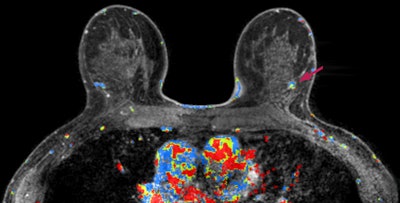

An MRI screening with a possible breast abnormality in the left breast (right side of the picture). Image courtesy of Carla van Gils, PhD."Although supplemental imaging increases the rate of cancer detection in women with dense breasts, the question remains whether it improves health outcomes," wrote lead author Marije Bakker, PhD, also from the Julius Center for Health Sciences and Primary Care, and colleagues.